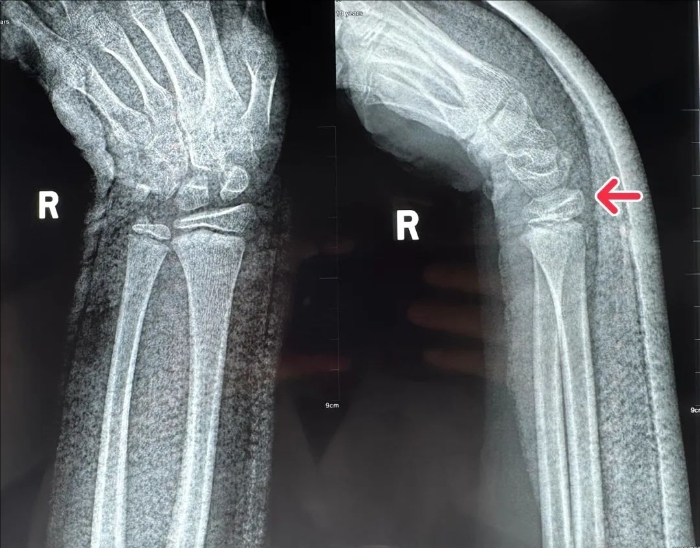

今年11月,一名10歲小孩不慎摔倒,導致右腕部腫脹疼痛、畸形、活動受限,被診斷為右橈骨遠端骨骺損傷。其父母接連跑了兩家醫院,都建議手術治療,然而,家長不愿意手術治療,怕給孩子生活、學習造成不便,于是輾轉求醫,來到我院骨科求診。

復位前

科主任姬傳磊接診后,發現患兒右腕腫脹畸形嚴重,如果不及時治療,將嚴重影響骨骼發育。他充分評估病情后,綜合考慮制定了周密、詳細的診療方案。

復位后

姬傳磊決定利用手法復位+石膏外固定的方法治療。復位后,再次行X線片檢查,可見骨折對位線良好,關節面平整。經過石膏固定1個月,患兒復查骨折位置良好,家長對姬傳磊主任讓孩子免受手術痛苦表達了誠摯謝意。